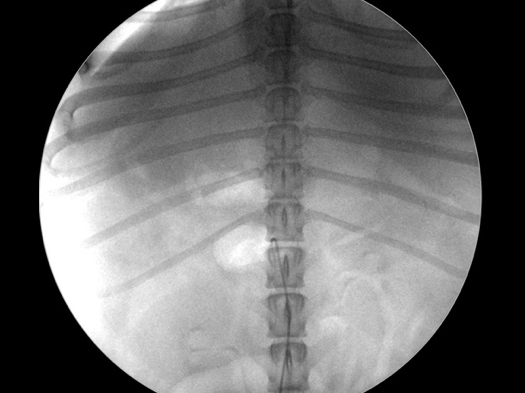

カテーテルを目的臓器まで挿入している様子